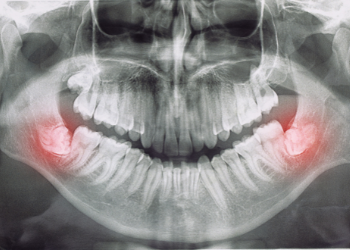

Wisdom teeth are also known as third molar teeth. They begin to emerge in the back of the upper and lower jaws, usually between the ages of 17 and 25 but have been known to show up for some people in their 40s or 50s!

For many people, wisdom teeth do not fully emerge, so many people feel extraction is not a necessary process. However, these unseen teeth can become impacted against adjacent molars or against your jaw. Our team can help assess your wisdom teeth to see if extraction is necessary.